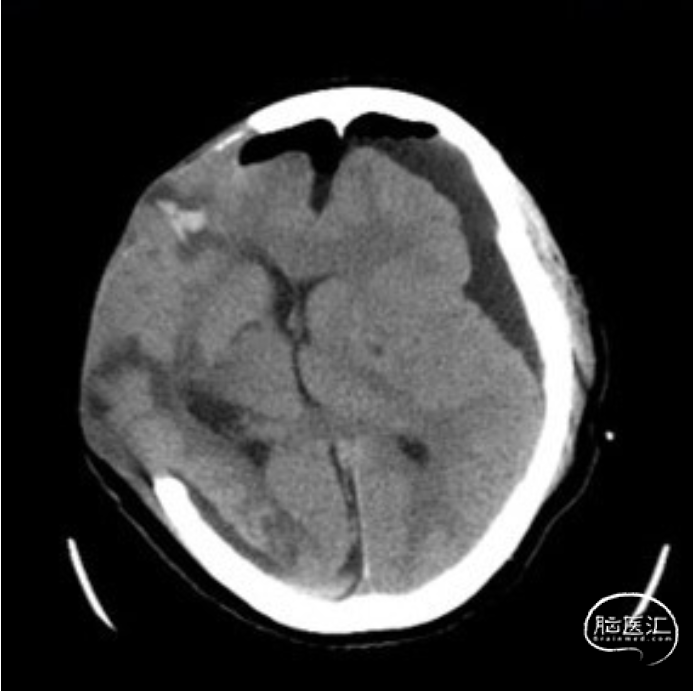

颅骨修补钛网修补术前后CT:术前术后颅内情况稳定。

颅骨修补钛网修补术后逐步拔除腰大池引流管和硬膜下引流管,拔管后患者病情稳定,意识清楚,顺利出院并转回当地医院康复治疗,术后多次复查头颅CT:颅内情况稳定,脑室稍有扩大。本例后期是否会出现脑积水,以及需要分流手术进一步干预,还有待进一步随访观察。